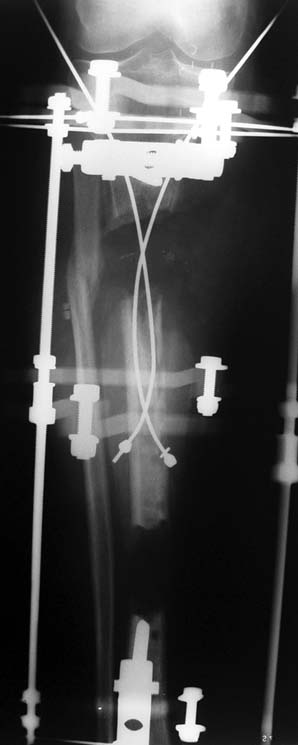

Recently, ilizarov techniques which is basis depend on distraction osteogenesis , bone segment transport or acute shortening after the resection at the site of pseudarthrosis combined with lengthening at another level of bone have been used. These treatment techniques may include some advantage for problems of infection, leg-length discrepancy, soft-tissue loss, and joint contracture.

Case 2